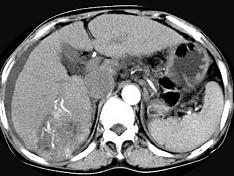

问题 女性,55岁,曾患乙肝,肝硬化多年,右上腹胀痛1月余,CT检查如图所示,最可能的诊断是 ( )

选项 A.肝硬化腹水、下腔静脉血栓形成 B.肝硬化腹水、胆管细胞癌 C.肝硬化腹水、肝癌并下腔静脉癌栓 D.肝硬化腹水、肝脓肿 E.肝硬化腹水、肝血管瘤

答案 C